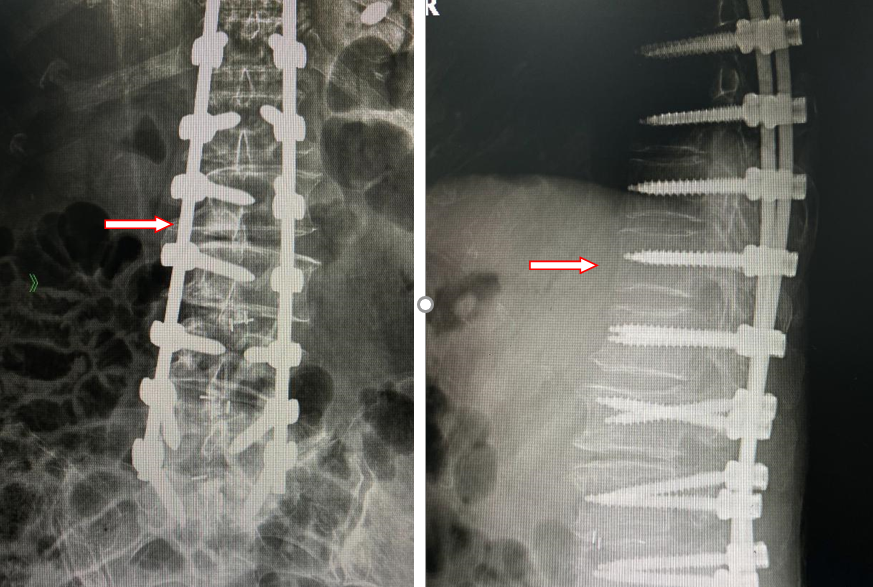

(术后,侧弯及后凸畸形纠正,恢复正常生理曲度)

许阿姨的情况比较严重,需要微创手术处理。手术的学名有点长,叫“脊柱后柱截骨矫形、椎弓根钉系统内固定术”。

简单说,就是要把畸形的脊椎骨进行截骨操作,修修补补,尽量让它们的形态、位置恢复正常,解放受压迫的神经,这样才能缓解甚至消除疼痛。

这个手术中必须使用一种固定螺钉,像桩子一样插进骨头里。而骨质疏松的骨头就好比松软的土壤,打进去的固定桩根本撑不住。稍有不慎,就可能发生更大的失血、脊髓神经的损伤(截瘫)风险。最终,在输血科、麻醉科等多学科协作下,许阿姨的手术做得很顺利。